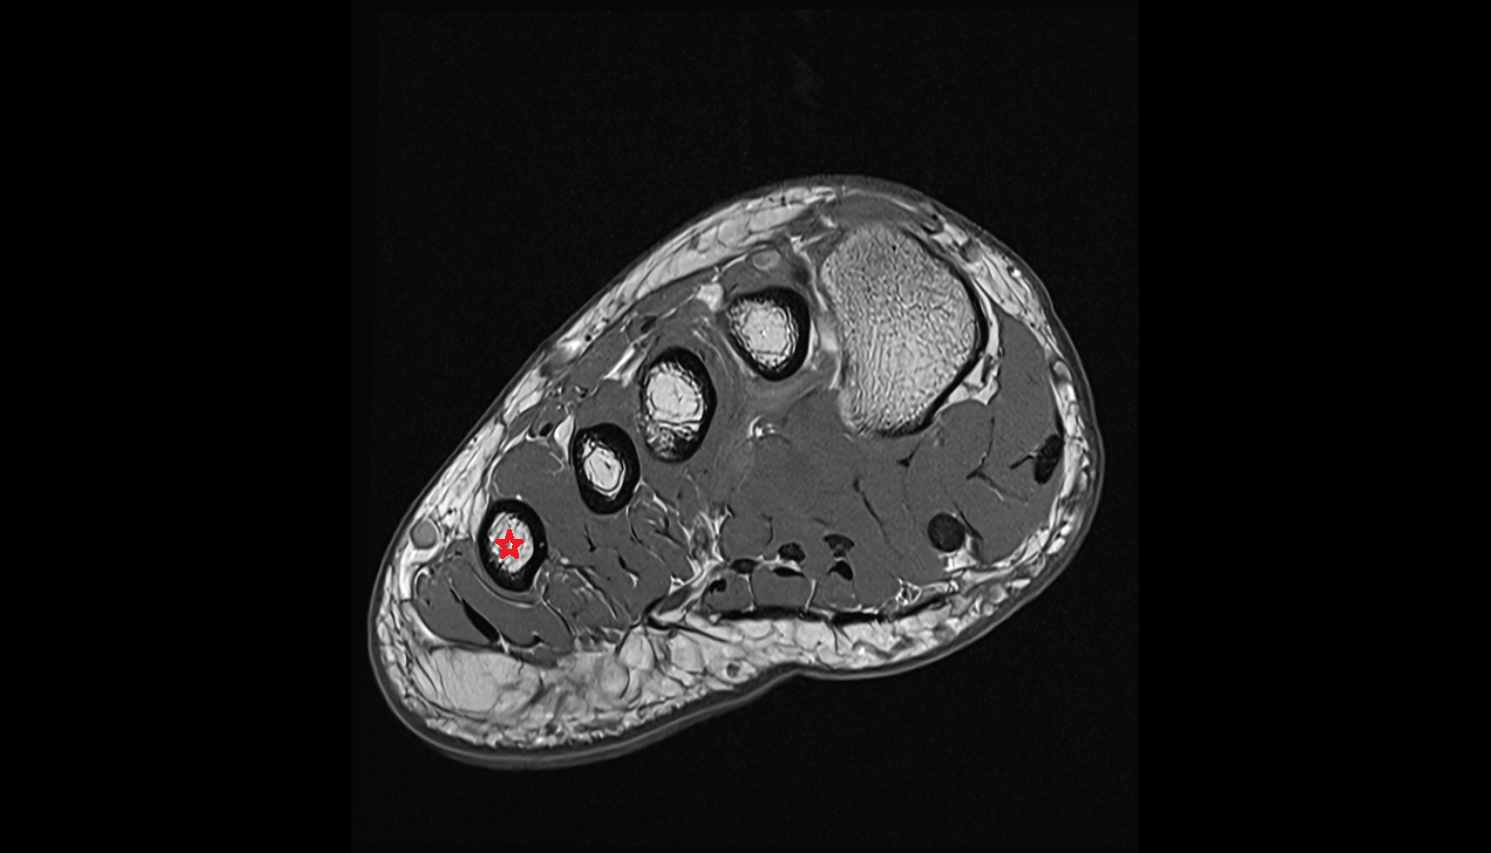

- Flexor hallucis brevis muscle

- Lateral head of flexor hallucis brevis muscle

- Medial head of flexor hallucis brevis muscle

- Adductor hallucis muscle

- Transverse head of adductor hallucis muscle

- Oblique head of adductor hallucis muscle

- Lumbrical muscles

- Plantar interosseous muscles

- Dorsal interosseous muscles